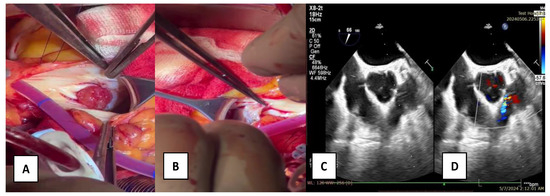

A 58-year-old male patient with multiple cardiovascular risk factors (high blood pressure, dyslipidemia, peripheral arterial disease, smoker) and a relevant family history (father had a myocardial infarction at age 56) with a history of pituitary adenoma surgery presented with persistent exertional dyspnea. TTE revealed a round, oval tumor attached to the pulmonary valve. The ejection fraction was estimated visually at 55%, with no segmental or global kinetic abnormalities and no signs of pulmonary thromboembolism (PE). The dyspnea persisted; therefore, the patient underwent coronary angiography, which revealed chronic occlusion of the circumflex artery, severe distal stenosis of the right coronary artery, and severe stenosis of the intermediate branch (Figure 1A,B). To accurately assess the tumor formation, the patient underwent cardiac MRI, which described a tumor formation (1.1 × 0.8 cm) as iso-/hypointense on T1-weighted sequences, mildly hyperintense on T2-weighted sequences, with no central enhancement but peripheral enhancement with gadolinium on delayed post-contrast sequences. These tissue characteristics supported the diagnosis of a papillary fibroelastoma (Figure 2A,B). Additionally, no other cardiac tumor structures were identified, and no signs of acute or chronic pulmonary embolism were detected. After obtaining the patient’s written consent and following discussions within the Heart Team, the patient underwent excision of the tumor formation from the pulmonary valve and coronary artery bypass grafting. Intraoperative transesophageal echocardiography (TEE) revealed a round, oval, mobile, well-defined tumor approximately 1.1 × 0.8 cm in diameter, attached to the surface of the right cusp of the pulmonary valve (Figure 1C,D). The tumor did not exert a hemodynamic impact on the valve, was not associated with pulmonary stenosis, and was accompanied by only mild pulmonary regurgitation. No other significant valvular pathologies were observed, and there was no echocardiographic evidence of PE. The surgical intervention was performed via sternotomy, under cardiopulmonary bypass with central cannulation: arterial in the ascending aorta and venous in the right atrium. Cardiac arrest was achieved using Calafiore cardioplegia. Initially, the distal coronary anastomoses were completed, followed by a longitudinal incision of approximately 4 cm in the pulmonary trunk to access the tumor. The tumor was friable, mobile, measuring approximately 1.1 × 1.0 cm, and attached to the pulmonary artery side of the right cusp of the pulmonary valve (Figure 3A). It was completely resected along with a small portion of the right pulmonary cusp that included its implantation base. Since only a small amount of valvular tissue was resected, valve repair was successfully performed using a continuous suture with 5.0 Prolene, Ethicon Inc., Cornelia, GE, USA, without the need for autologous pericardium or other biological materials (Figure 3B–D). Subsequently, the proximal coronary anastomoses were completed. No residual pulmonary regurgitation was detected. No other tumor formations were detected intraoperatively. The macroscopic appearance of the tumor was similar to a sea anemone when placed in serum (Figure 4A). The diagnosis of papillary fibroelastoma was confirmed by histopathological analysis (Figure 4B,C). The postoperative course was favorable and without complications, and the patient was discharged without further complaints of dyspnea.

Figure 4. The postoperative characteristics of the papillary fibroelastoma. (A)—the “sea anemone” macroscopic aspect; (B,C)—microscopic examination reveals multiple avascular villous projections (B) covered by endothelial cells (C).